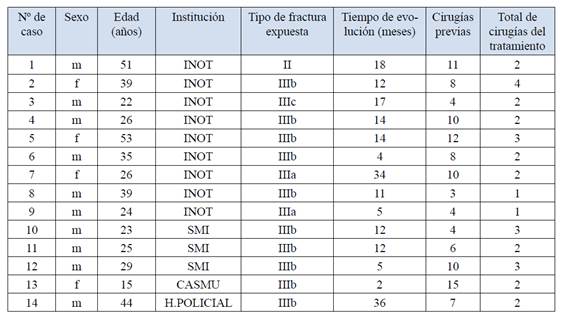

Del total de pacientes, 4 eran mujeres y 10 eran hombres. La media de edad fue 32,2 años (15-53). Los centros asistenciales de procedencia de los pacientes fueron: INOT (Instituto Nacional de Ortopedia y Traumatología) 9 pacientes, SMI (Servicio Medico Integral) 3 pacientes, CASMU (Centro de Asistencia del Sindicato Médico del Uruguay) y Hospital Policial 1 paciente cada uno. (Tabla 1)

La lesión inicial en los 14 pacientes fue la fractura expuesta: Gustilo tipo IIIb con 10 pacientes, seguido de la IIIa con 2 pacientes, 1 paciente con fractura tipo II, y 1 paciente con tipo IIIc.

El tiempo promedio de evolución fue de 14 ± 10,1 meses (entre 2 y 36 meses).

El número de cirugías previas promedio fue de 8 (entre 3 y 15).

El seguimiento promedio fue de 13 meses (entre 6 y 27 meses).

Las cirugías totales requeridas por el tratamiento de transporte óseo fueron de 1 para 2 pacientes, 2 para 8 pacientes, 3 para 3 pacientes y 4 para 1 paciente, las mismas correspondieron a colocación de montaje y osteotomía, revisión del sitio, acoplamiento e injerto autólogo, a veces colocación de placa bloqueada y osteotomía de realineación.

Doce pacientes (86%) tuvieron como patología de ingreso al protocolo pseudoartrosis infectada y en 2 pacientes (14%) fractura expuesta IIIB. Los gérmenes encontrados fueron Staphylococcus Aureus Meticilino Sensible y Meticilino Resistente, Pseudomona Aeruginosa, Acinetobacter, E. Coli y Flora Polimicrobiana a predominio Gram-. La perdida ósea mostró una media de 6,7±2,0 centímetros (mínimo 4 y máximo 11 centímetros).